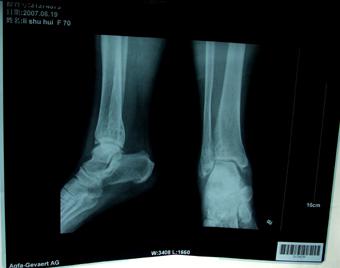

(图:三个疗程结束后,X光片检查患者踝关节恢复正常)

治疗2天后,张先生的疼痛就没有之前那么剧烈了,7天后疼痛又有所减轻,脚部肿胀有了消退表现。在治疗一个疗程结束后踝关节肿胀现象明显消失,已经可以缓慢行走,疼痛的剧烈程度大幅度下降。两个疗程结束后,张先生的踝关节基本恢复正常状态,行走没什么问题。三个疗程治疗结束后复查显示,C-反应蛋白降至2.69mg/L,血沉下降至20mm/h,其他检验指标正常,踝关节肿胀部位有效恢复正常,疼痛也已消失,可以正常走路。